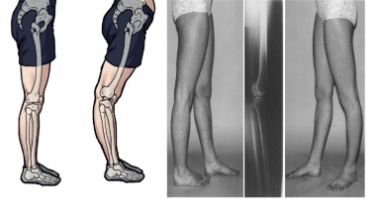

오다리, 또는 의학적 용어로 '외반슬'은 무릎 사이의 간격이 3cm 이상 벌어져 다리가

오자 형태로 보이는 체형을 의미한다.

이는 '진짜 오다리'와 '가짜 오다리'로 구분된다.

- 진짜 오다리: 뼈 자체가 변형된 경우이다.

- 가짜 오다리: 근육 불균형이나 무릎 과도한 펴짐 등으로 인해 발생한다.

1. 진짜 오다리 (뼈 자체의 변형)

- 뼈 자체가 변형되어 무릎 사이 간격이 벌어지는 경우이다.

이런 경우 운동이나 교정 치료로는 증상 호전이 어렵다.

2. 가짜 O다리 (구조적 회전)

- 다리 뼈 자체에는 문제가 없지만, 다리의 구조적 회전으로 인해

오자 형태가 나타나는 경우로 이런 경우 운동 교정 치료로 증상 개선이 가능하다.

3. 가짜 O다리의 특징

- X-ray 상 무릎 뼈가 안쪽으로 돌아가 있다가 발을 바깥쪽으로 돌리면

무릎이 정면을 향하며 다리가 붙는 체형으로

즉, 무릎이 안쪽으로 회전되어 오다리처럼 보이게 만드는 경우이다.